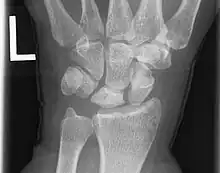

La radiographie est fréquemment normale à la phase initiale de la maladie[2]. La scintigraphie osseuse se montre alors plus sensible en mettant en évidence une hyperfixation en regard du lunatum. L'IRM permet également le diagnostic précoce en révélant des anomalies de signal du lunatum, ce dernier apparaissant en hyposignal T1 et hypersignal en densité de protons[2].

Sur les formes plus évoluées, la radiographie permet le diagnostic de la maladie. Les anomalies radiographiques sont regroupées dans la classification de Lichtman[2] qui reflète l'évolution de la maladie :